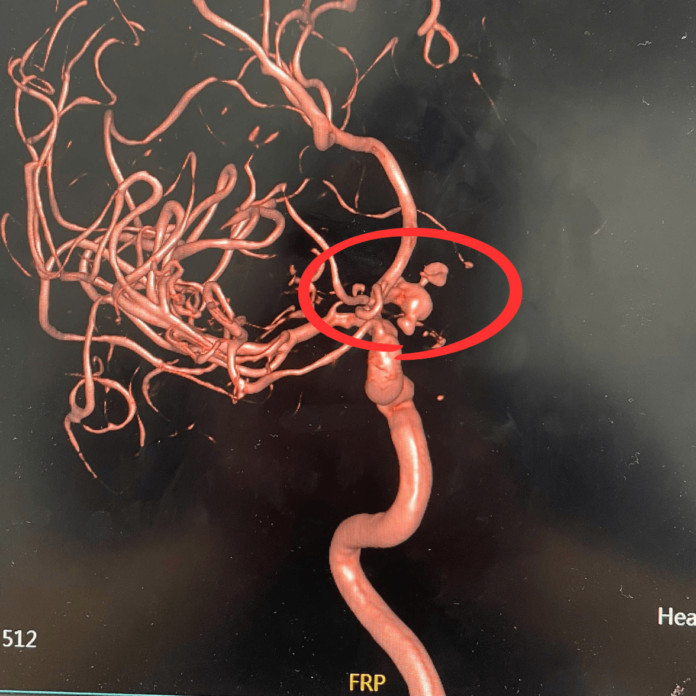

phinh-mach-3.jpg

Hình ảnh DSA mạch não sau can thiệp nội mạch xử trí túi phình bằng coil có hỗ trợ stent - Ảnh BVCC